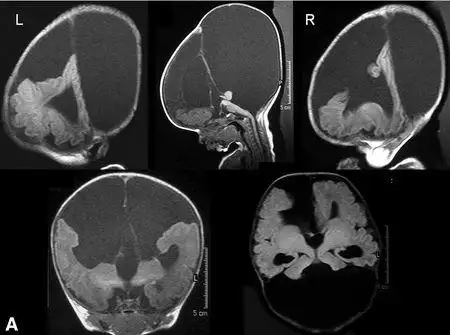

中央变异型前脑无裂畸形鉴别诊断_医学界-助力医生临床决策和职业成长

全前脑畸形_颅脑先天畸形_颅脑先天畸形相关疾病 - 好大夫在线